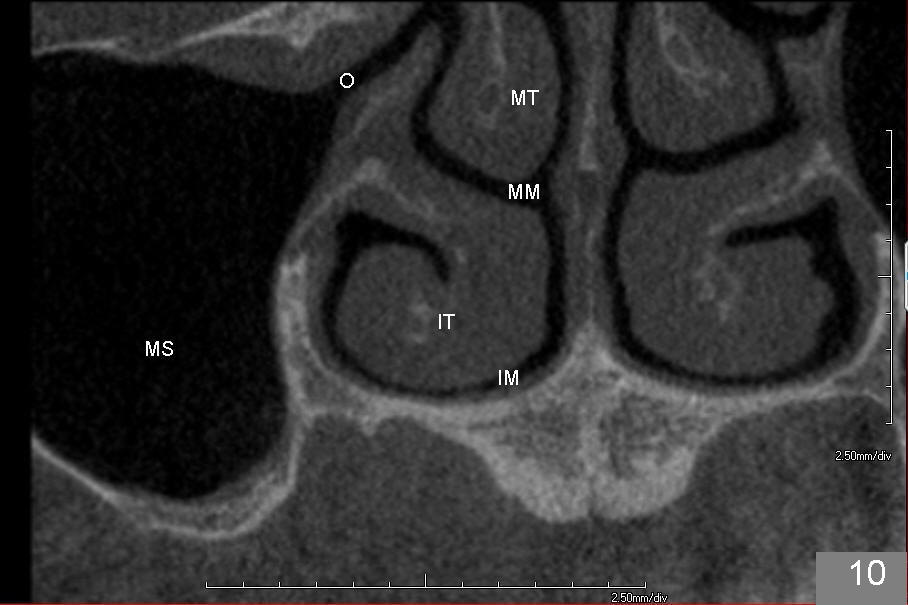

上颌窦手术后,病人即刻汇报患侧鼻塞,拍摄全景片,看不出来问题。给病人上颌窦术后医嘱,开喷鼻药(Afrin)和激素(Medrol Dosepak,减少水肿)。之后研究术前CT(图十至十二),但愿上颌窦分离内侧壁没有太过分。第二天鼻塞消失,病人并没有用喷鼻药,但是使用激素。